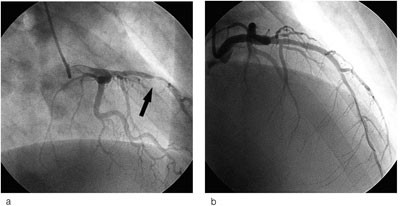

Pasienten fikk acetylsalisylsyre, klopidogrel og nitroinfusjon etter prosedyre for akutt koronarsyndrom. Blodprøver tatt etter ni timer viste forhøyede nivåer av myokardskademarkører. Troponin-I var da 2,5 µg/l (normalt < 0,05 µg/l) og CK-MB masse 115 µg/l (normalt < 5 µg/l). Koronar angiografi ble utført 12 timer etter smertedebut. Denne viste nærmest totalt okkludert midtre del av ramus interventricularis anterior (LAD) og trombedanning, i tillegg til generelle veggforandringer. Stenosen ble behandlet med perkutan koronar intervensjon (PCI) med stentinnleggelse, med godt angiografisk resultat (fig 2). Etter prosedyren steg verdiene for troponin-I til 9,8 og CK-MB masse til 133 µg/l. Telemetriovervåking registrerte to løp med kortvarig ventrikulær takykardi. Pasienten var ikke hemodynamisk påvirket av dette.